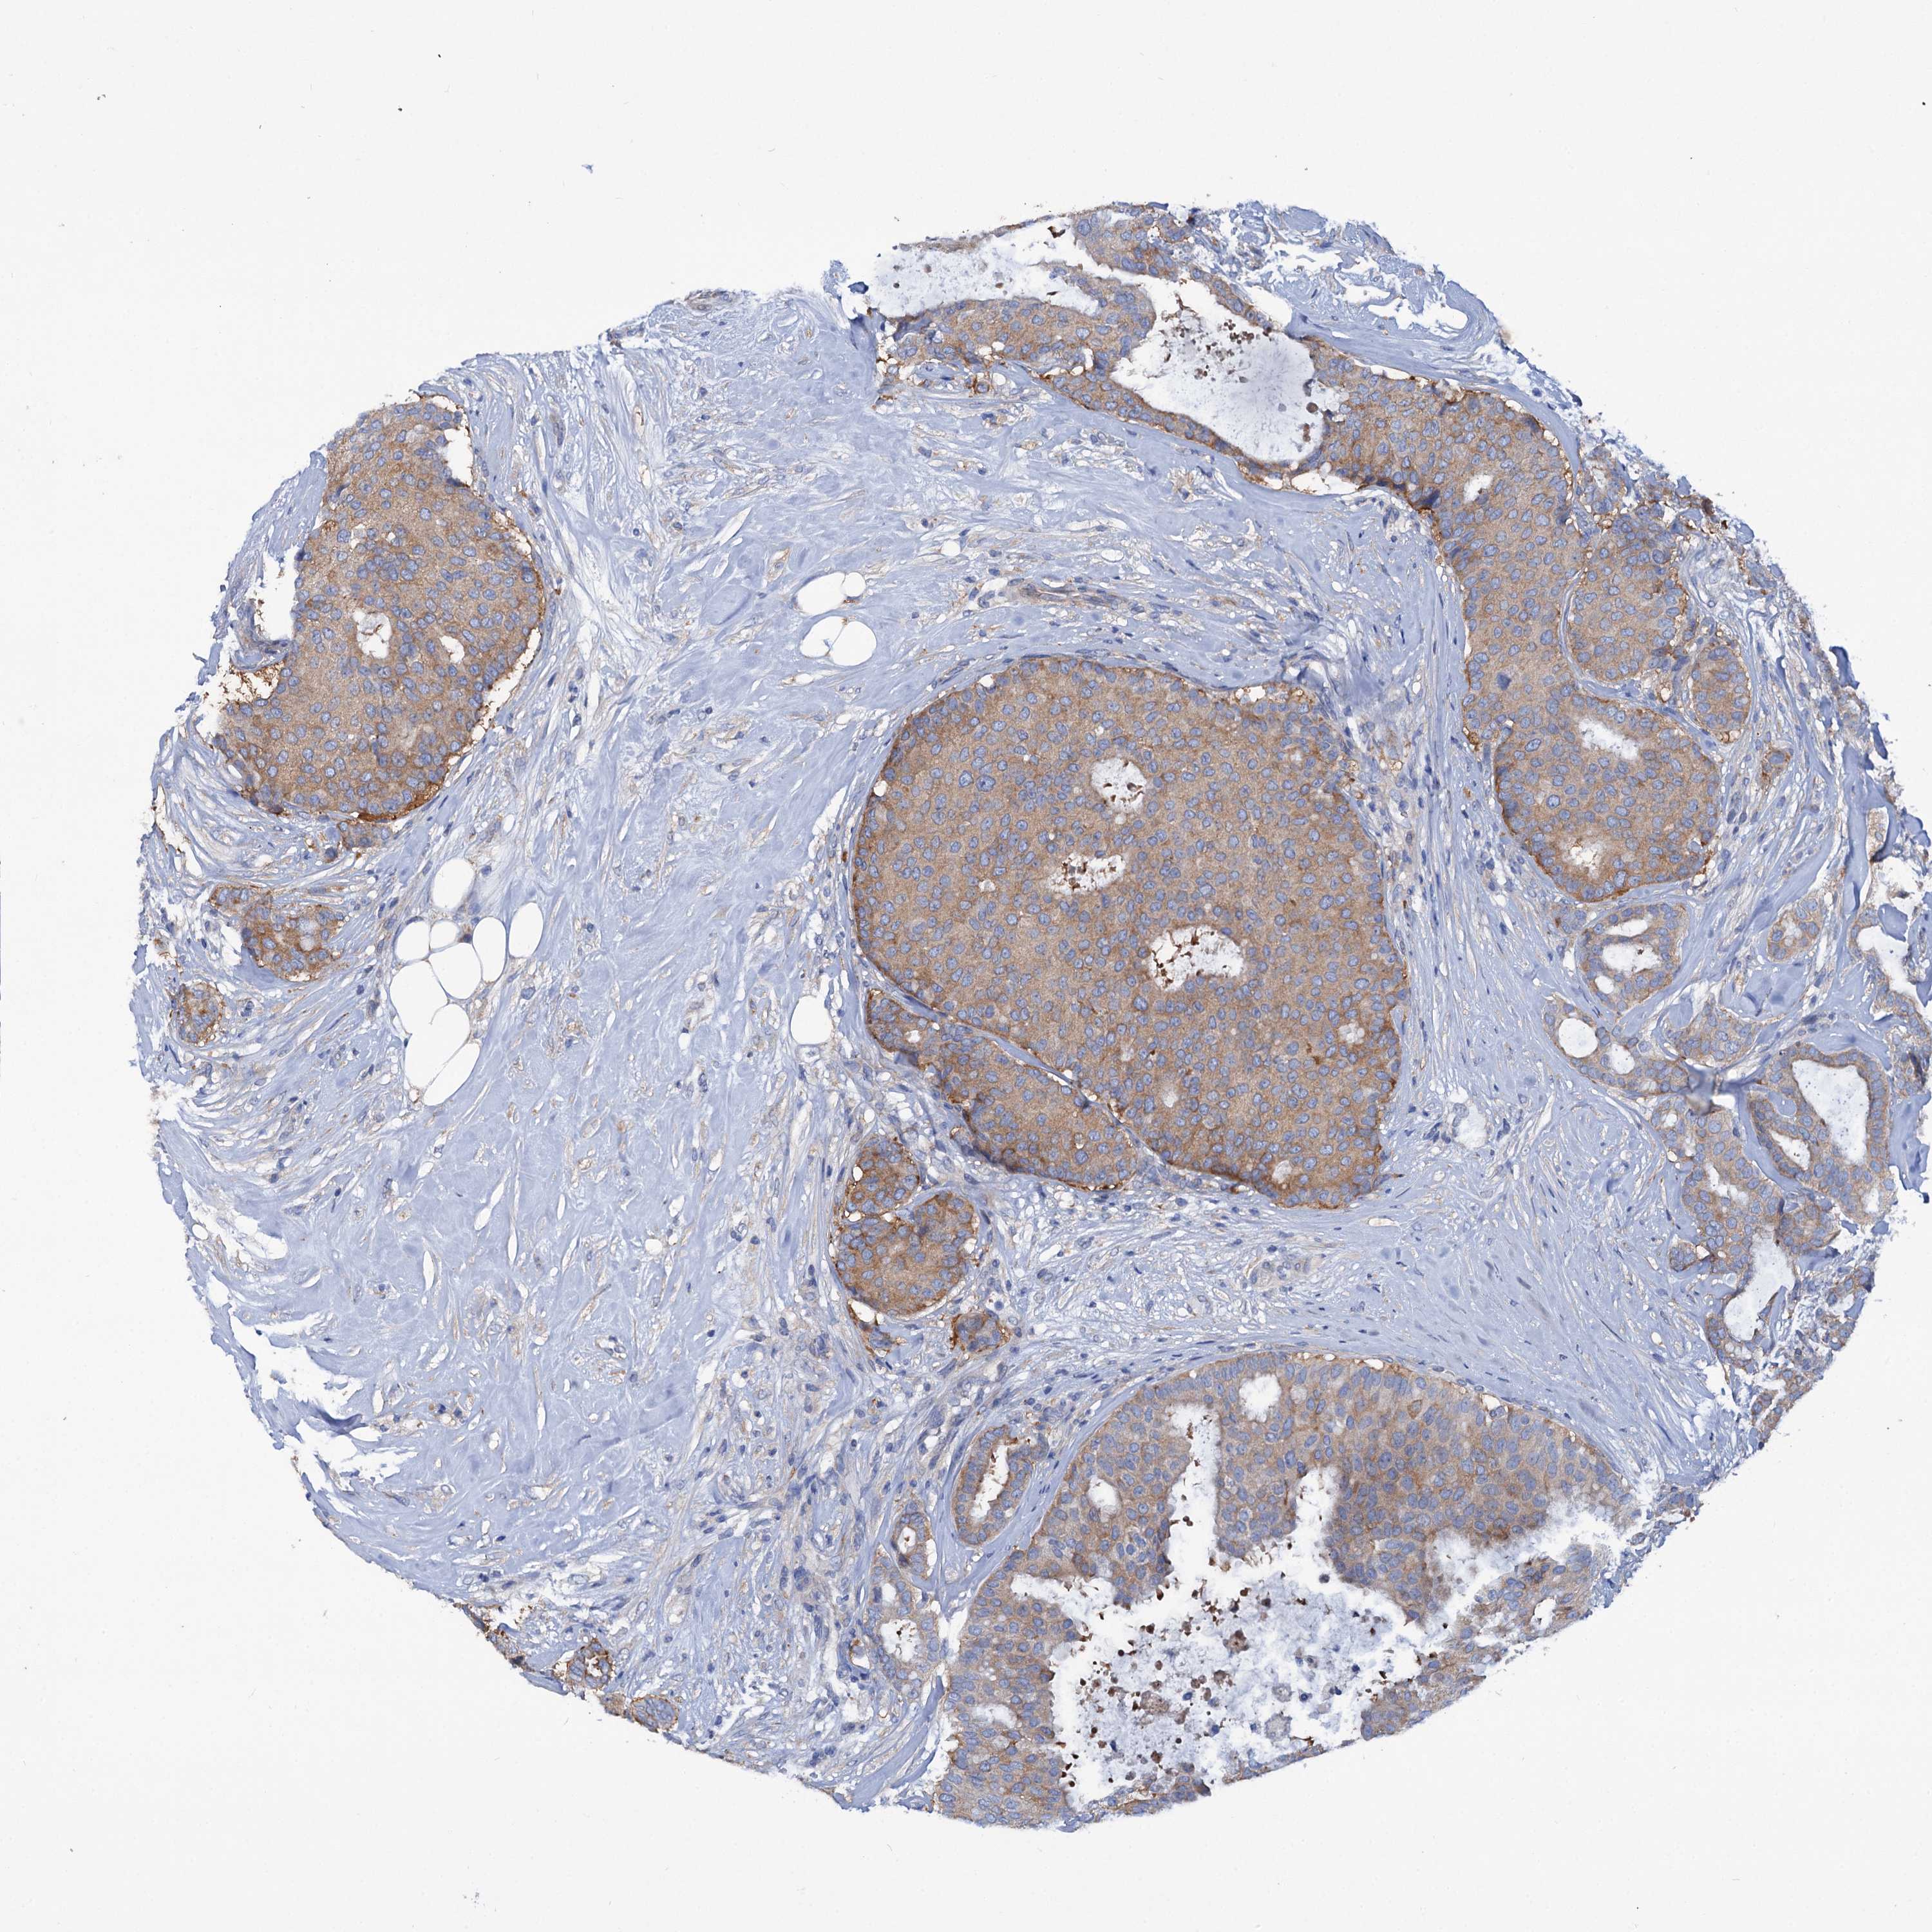

CANCER BREAST CANCER Show tissue menu

BRCA TCGA BRCA VALIDATION PROTEIN EXPRESSION

ANTIBODIES

AND

VALIDATION